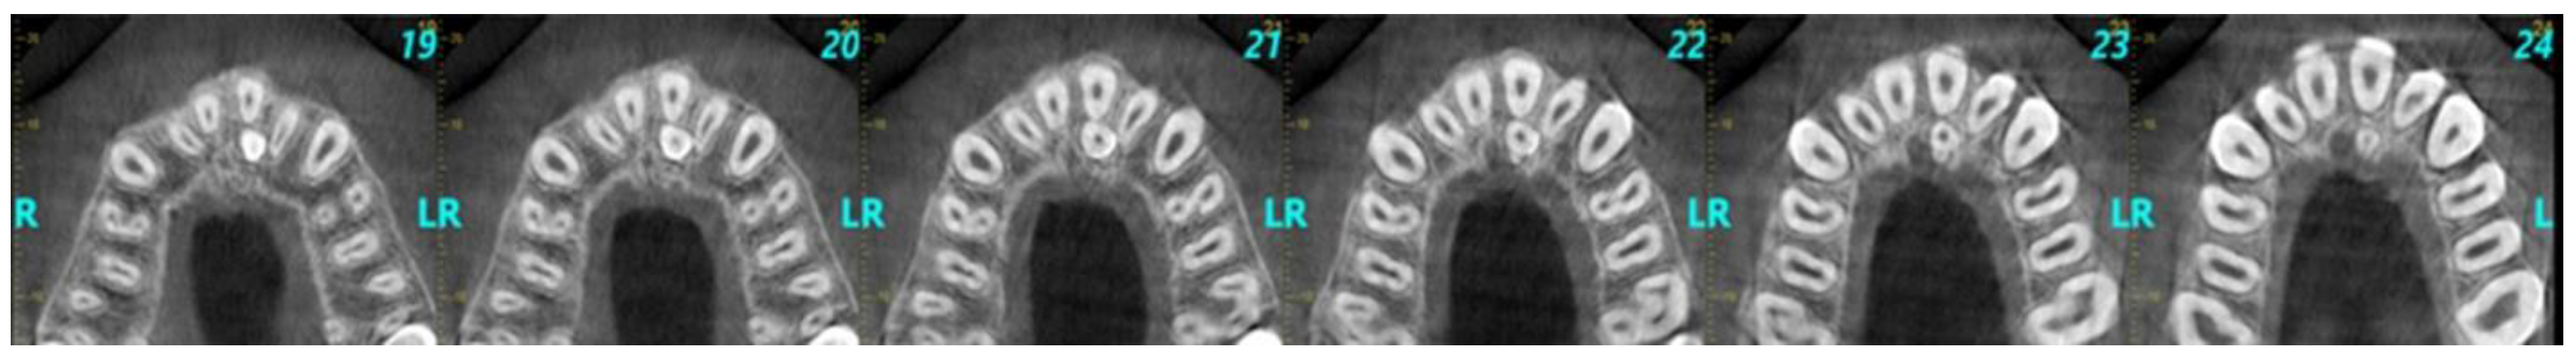

2.5. CBCT Scans’ Evaluation, Data Collection, and Extraction

- Number, size, shape, and location of the supernumerary teeth detected in the maxillary anterior area.

- Spatial orientation of supernumerary teeth in the sagittal plane.

- Relationship and proximity of supernumerary teeth to adjacent anatomical structures and adjacent teeth.

- Implications of supernumerary teeth on the dental arch.